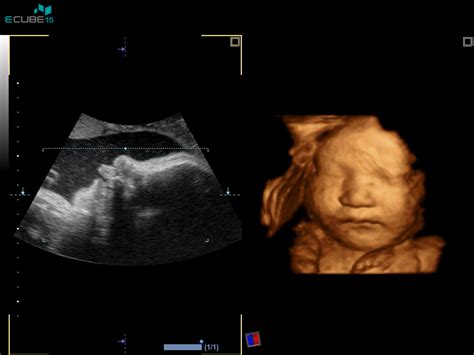

Pregled v 32. tednu nosečnosti

Pregled v 32. tednu nosečnosti je pomemben korak v zadnjem trimesečju. Poleg standardnih meritev telesne teže, krvnega tlaka in analize urina, se lahko opravi dodatna ultrazvočna preiskava za oceno rasti ploda. V tem tednu se telo in otrok intenzivno pripravljata na porod, tudi če se ta še zdi oddaljen. Otrok se v tem času pogosto obrne z glavo navzdol, kar je idealen položaj za porod. Simptomi, kot so zgaga in lažni popadki (Braxton Hicks), lahko postanejo izrazitejši. Telesna teža nosečnice se lahko poveča, kar je posledica rasti otroka, povečane količine plodovnice in drugih telesnih sprememb.

V zadnjem mesecu nosečnosti se intenzivno pogovarjamo o porodu. V 37. in 39. tednu nosečnosti se lahko opravi brezplačna kontrola kondicije ploda s kardiotokografijo (CTG) in ultrazvočno preiskavo, ki vključuje oceno plodovnice, zrelosti posteljice in oskrbe ploda s kisikom preko Dopplerja popkovničnih žil.

Poleg standardnih pregledov, so na voljo tudi samoplačniški ultrazvočni pregledi, ki omogočajo podrobnejšo oceno plodove rasti, stanja pri tvegani nosečnosti, merjenje pretokov skozi žile ploda in popkovino, ter merjenje materničnega vratu. V primeru specifičnih situacij, kot je medenična vstava ploda ali dvojčki, se lahko nudijo posebna posvetovanja.